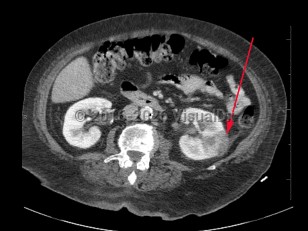

Intraabdominal abscessIntraabdominal abscess